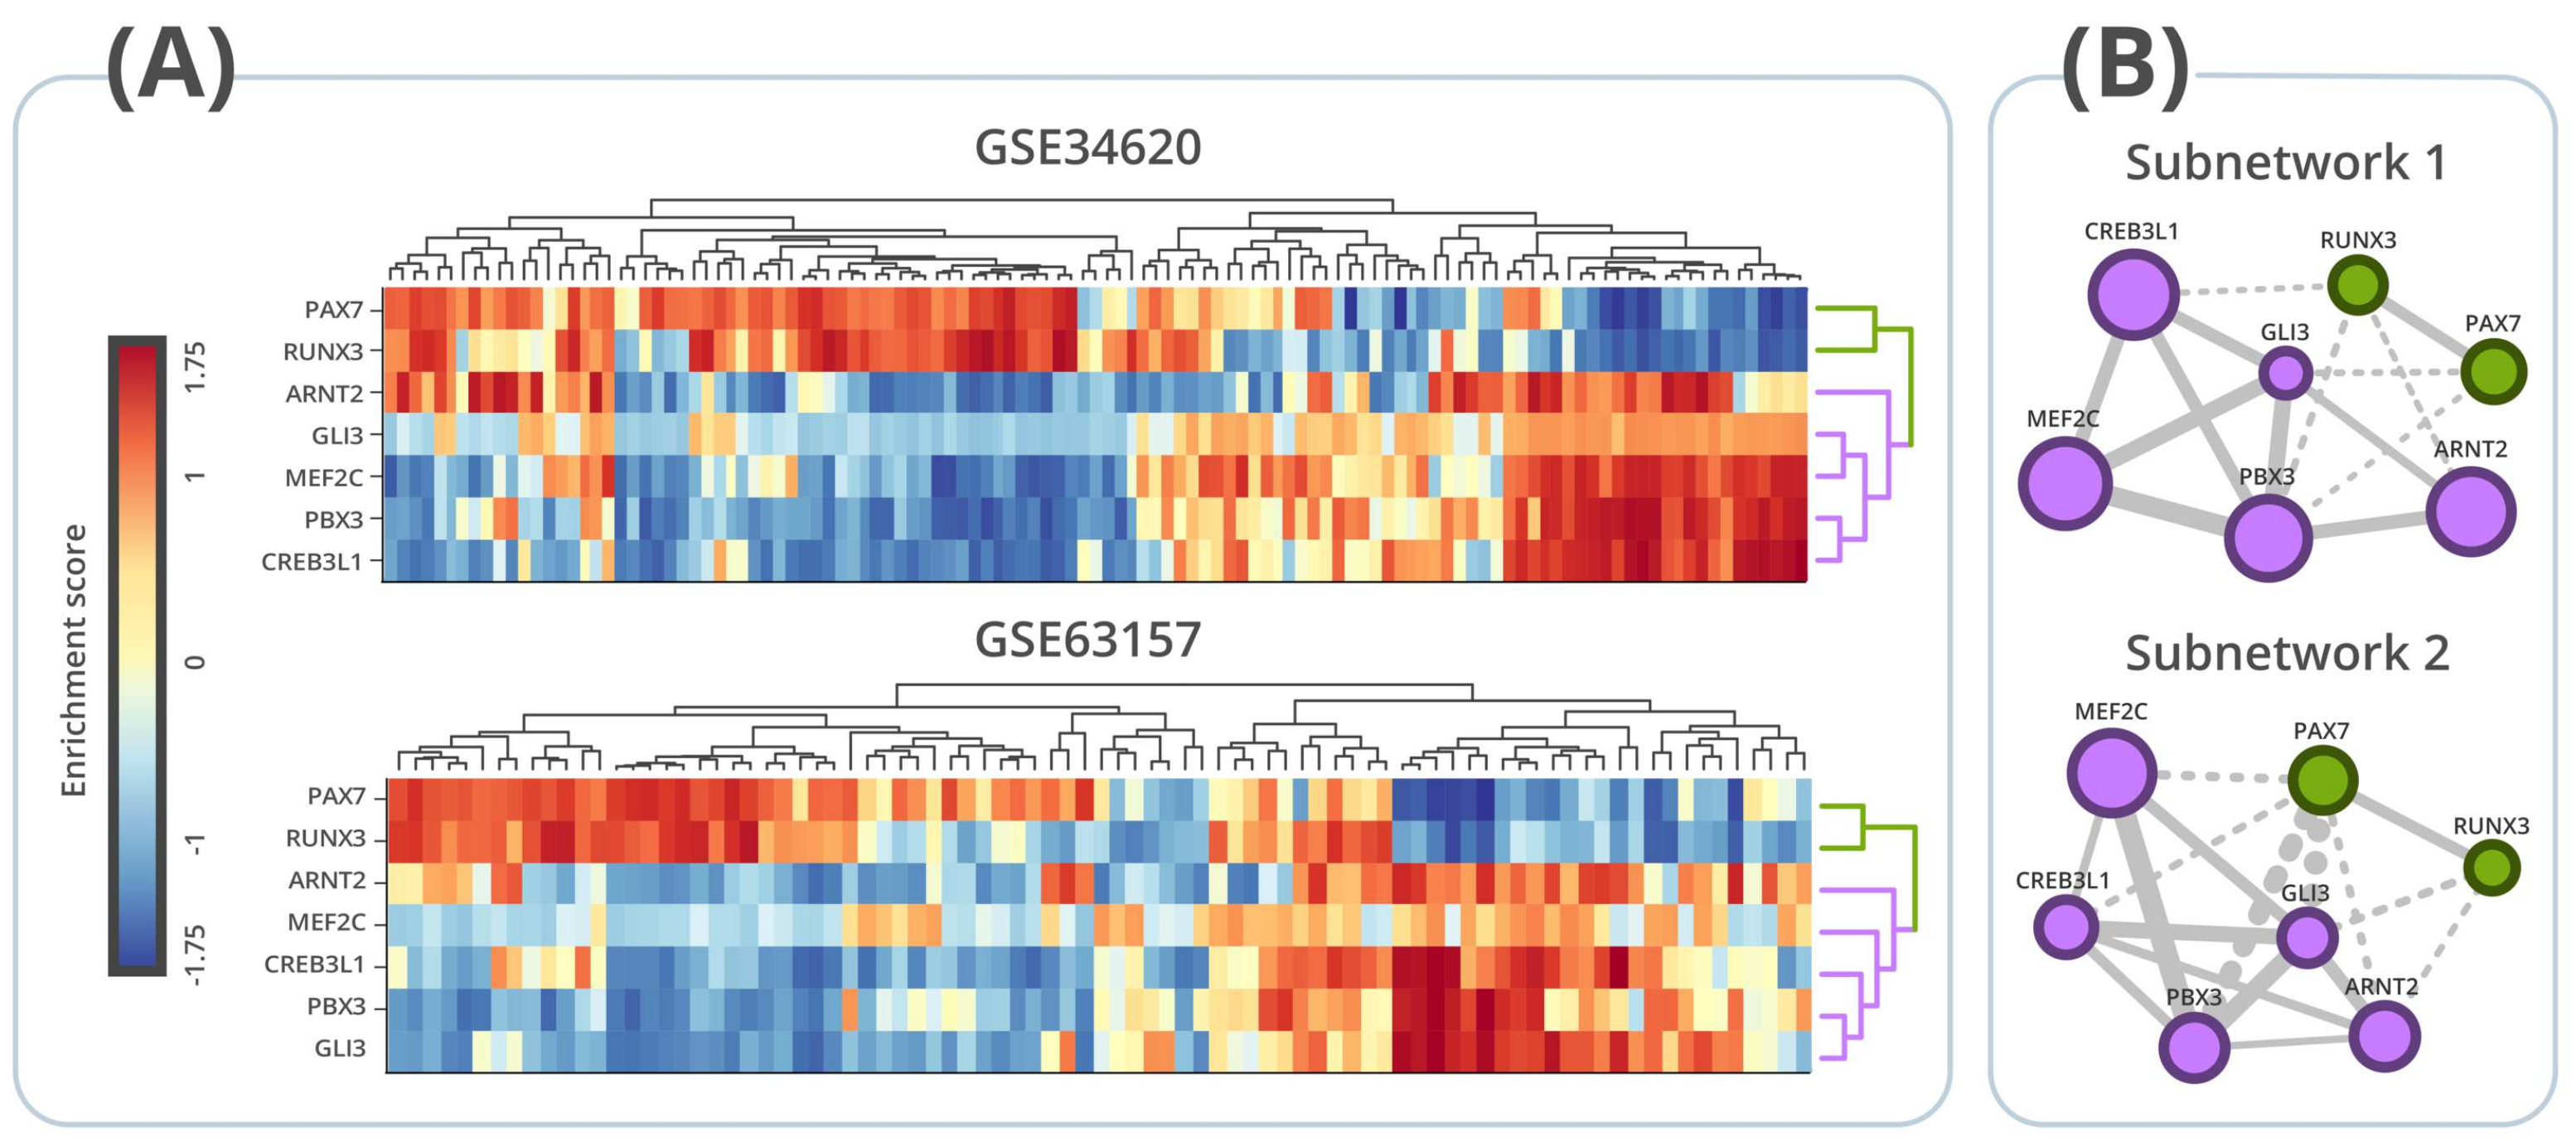

3.4. Regulon Activity

3.5. Survival Analysis